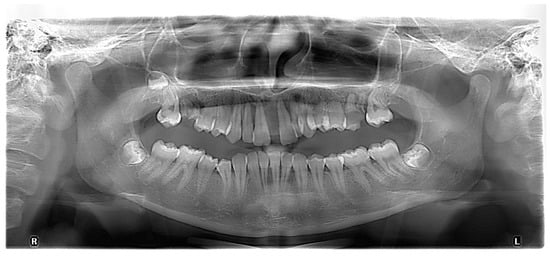

The plaque index score registered and bleeding upon probing (BOP) were 100%. The initial probing depth (PD) was 10 mm at the left central incisors (mesial) and 8–9 mm at the other proximal sites of the both upper central incisors. The tooth mobility (Miller Classification) was Class 2 for both the maxillary central and lateral incisors (Figure 2).

The initial radiography showed severe bone loss on the maxillary anterior tooth (Figure 3). In addition to the periodontal aspects, dental malposition of the maxillary and mandibular central and lateral incisors, deep bite malocclusion, deep hard palate, and advanced carious lesion in both maxillary first molars were observed. It was also not possible to specify whether the bone resorption in the anterior area was related to the trauma, considering that after the trauma, the patient did not request dental treatment.

The periodontal diagnostic was stage III, grade C periodontitis. Stage III of periodontitis, in this case, was defined based on the severity (interdental CAL ≥ 5mm, radiographic bone loses extending to the apical third of the root) and complexity of management (probing depth > 6 mm, vertical and horizontal bone loss, tooth mobility degree ≥ 2, and masticatory dysfunction). The grade of periodontitis was estimated with direct or indirect evidence of % bone loss/age > 1.0 and destruction exceeding biofilm deposits (suggestive of rapid progression and early onset disease) [12,13,14]. The orthodontic diagnostic was class II, division 1 malocclusion (Angle classification) and deep bite malocclusion, with dental malposition primary and secondary to the periodontal disease. The smile line was altered due to the overgrowth of gingival tissue at the maxillary tooth. Additionally, following vitality and percussion tests, both the maxillary and mandibular incisors were vital and without any signs of pulpal involvement.